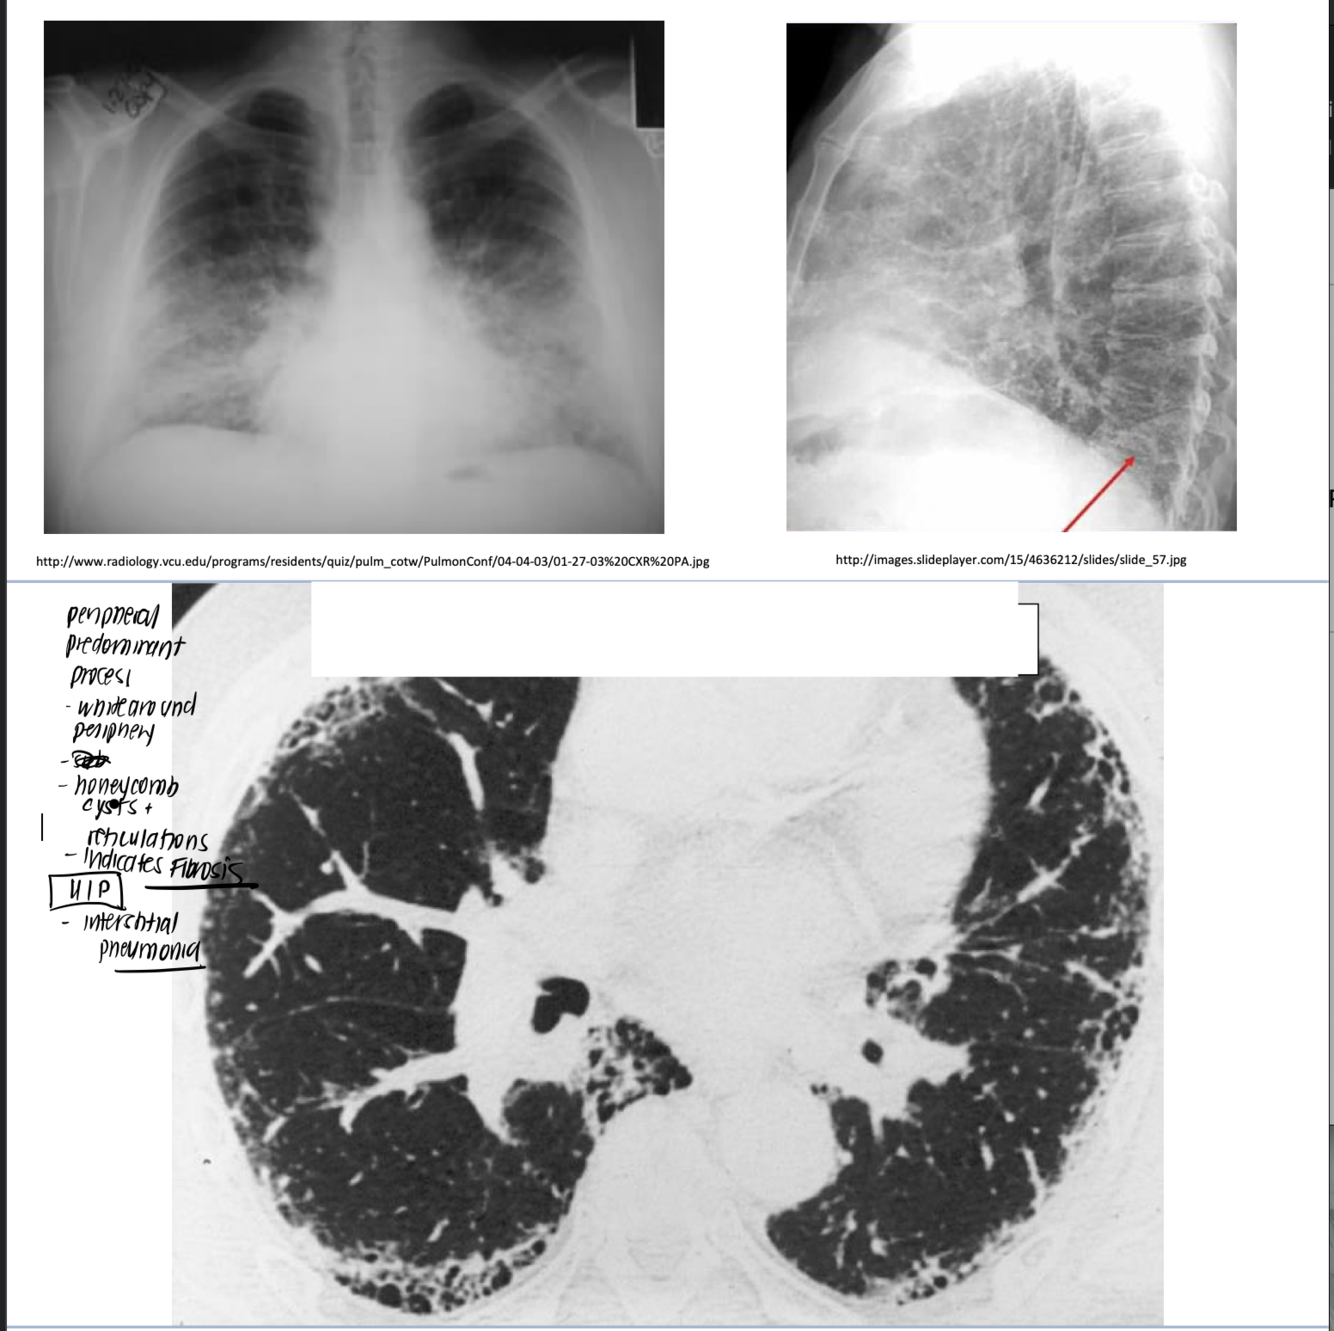

thick fibrosis on the periphery of the lung.

• ILD encompass a complex group of diseases

• Idiopathic Pulmonary Fibrosis

characteristic clinical/radiological presentation • New drugs available! (a disease with a poor prognosis)

Correct Diagnosis of ILD very Important (usually requires Path)

• Most common ILD • Characteristic pathology can confirm the diagnosis

• Some cases can be diagnosed with a very

distribution of honeycomb lung for UIP

UIP encompasses which diseases

honey comb lung, usually indicates ILD– fibrosis